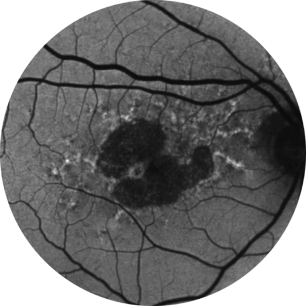

Avaliação inicial Ano 1

BCVA 20/63+, área de AG de 5,18 mm2

Avaliação inicial Ano 2

BCVA 20/80-2, área de AG de 10,39 mm2

Avaliação inicial Ano 5

BCVA 20/200, área de AG de 18,58 mm2

As imagens são cortesia do Dr. David Elchenbaum, da Retina Vitreous Associates of Florida.

BCVA = melhor acuidade visual corrigida (best corrected visual acuity).